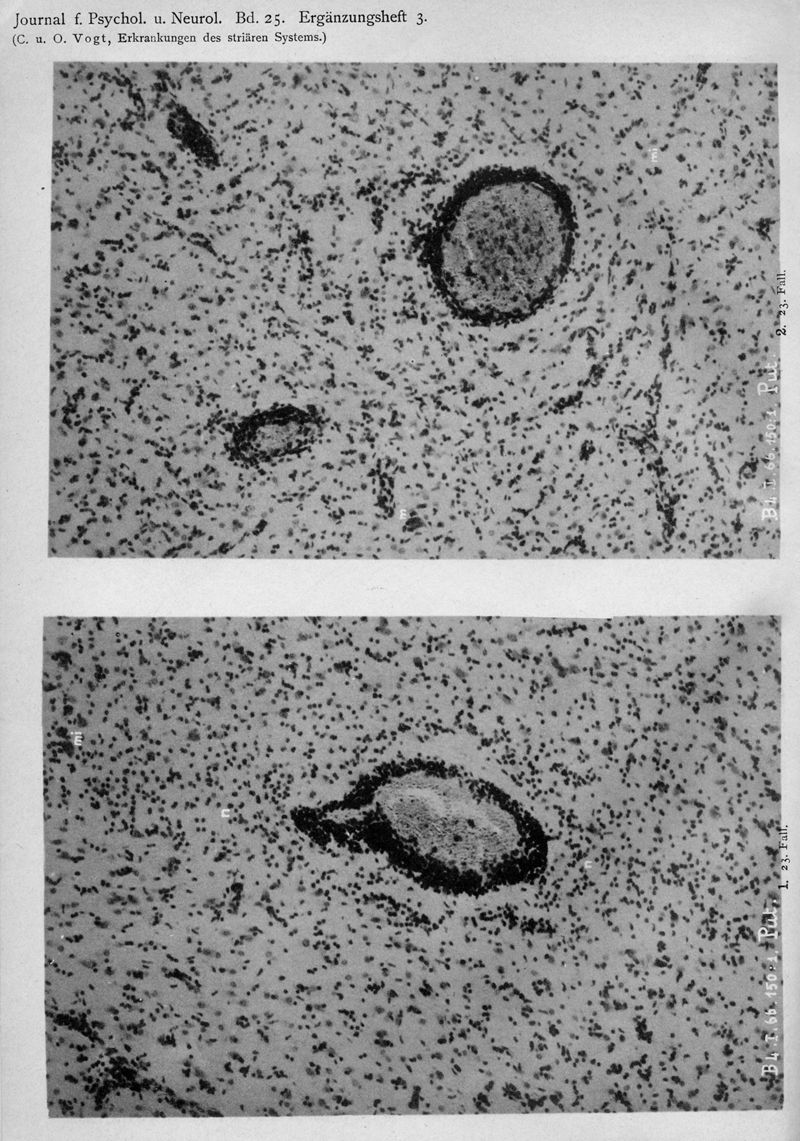

VOGT, Cécile / VOGT, O.

In : Journal für Psychologie und Neurologie,

1920, Vol. 25, pp. 627-846